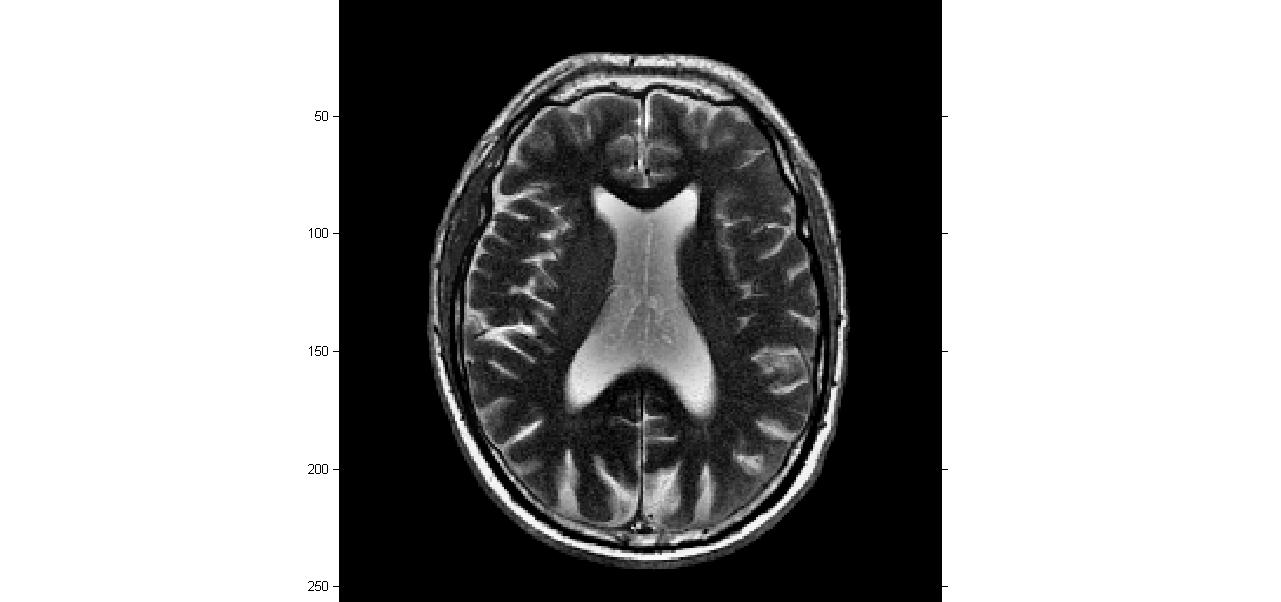

三、运行结果